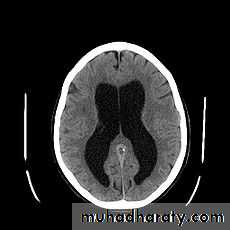

Hydrocephalus

Hydrocephalus also known as "water on the brain", is a medical condition in which there is an abnormal accumulation of cerebrospinal fluid (CSF) in the ventricles, or cavities, of the brain.This may cause

increased intracranial pressure inside the skullprogressive enlargement of the head

Hydrocephalus can be caused by impaired cerebrospinal fluid (CSF) flow, reabsorption, or excessive CSF production.

Communicating hydrocephalus, also known as non-obstructive hydrocephalus, is caused by impaired cerebrospinal fluid reabsorption in the absence of any CSF-flow obstruction between the ventricles and subarachnoid space. Various neurologic conditions may result in communicating hydrocephalus, including subarachnoid hemorrhage , intraventricular hemorrhage, meningitis and congenital absence of arachnoid villi..

Non-communicating or obstructive hydrocephalus, is caused by a CSF-flow obstruction ultimately preventing CSF from flowing into the subarachnoid space (either due to external compression or intraventricular mass lesions).